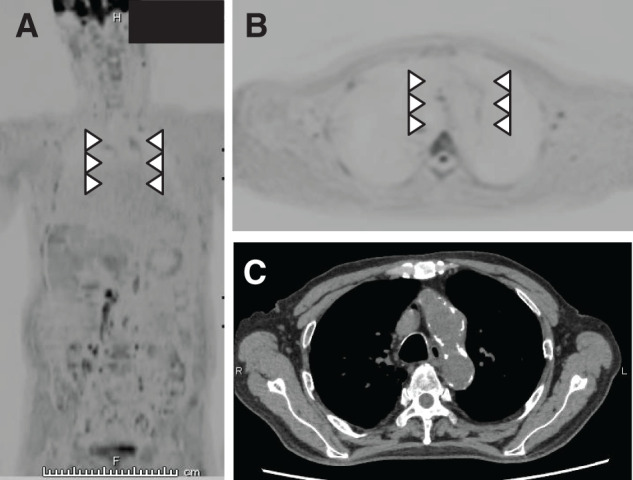

Diffusion-weighted whole-body imaging with background body signal suppression has been used to diagnose fever of unknown origin. An 86-year-old man who underwent bile duct jejunostomy for bile duct cancer presented with fever (body temperature, 40°C). Escherichia coli was detected in blood cultures. Diffusion-weighted whole-body imaging with background body signal suppression revealed accumulation in the aortic arch. Therefore, infectious aortitis secondary to retrograde cholangitis was diagnosed. The patient was treated with antibiotics, and the aortic arch accumulation disappeared. Diffusion-weighted whole-body imaging with background body signal suppression is a useful modality for diagnosing vasculitis and assessing treatment effectiveness.